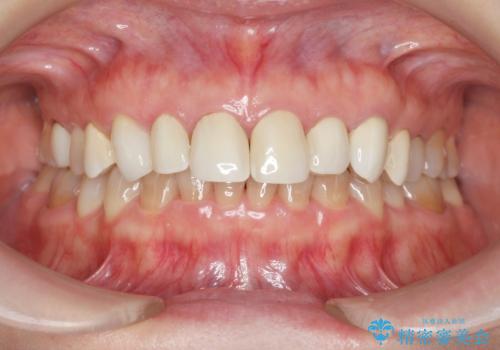

ラミネートよりもより透明感の再現性の高いジルコニアクラウンの出来に喜んでいただくことが出来ました。